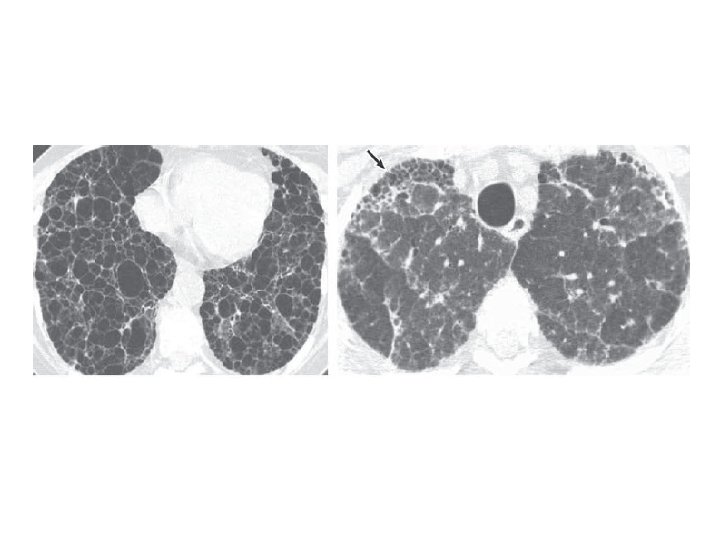

HRCT features of UIP/IPF • Basal/peripheral predominance • Reticular lines • Traction bronchiectasis • Honeycombing • ± Ground glass

CT features not suggestive of UIP